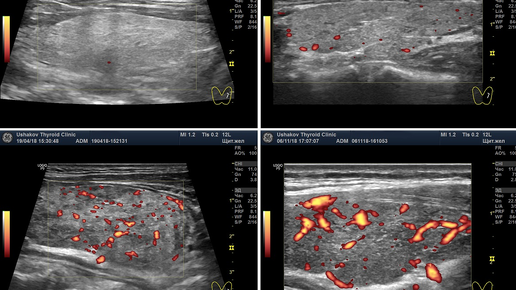

Цветовое допплеровское картирование (ЦДК) – это разновидность УЗИ, которая основана на эффекте Допплера. На экране монитора видно выделенное цветом движение жидкости по протокам. Показания к проведению Процедура цветного допплеровского картирования назначается пациенту при подозрении на многие виды заболеваний. Часто данную процедуру назначают во время беременности для оценки состояния мамы и малыша. Во время беременности это такие ситуации, когда: Показания для УЗИ с ЦДК: УЗИ щитовидной железы...

Во время УЗИ щитовидной железы врач обязан провести допплерографическое исследование каждой доли и перешейка, а также определить скорость кровотока в сосудах железы. Это исследование врачи обозначают аббревиатурой ЦДК или ЭДК (ЭД). ЦДК - цветовое допплеровское картирование, ЭДК - энергетическое допплеровское картирование (иногда применяют краткое обозначение - ЭД). ЭДК более точно, без искажений, позволяет определять кровоток. Следует знать, что допплеровское исследование щитовидной железы является обязательной, важной частью при УЗИ...

При УЗИ щитовидной железы оценивайте кровоток!